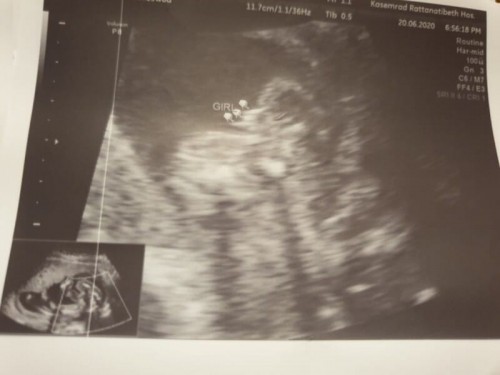

อัลตราซาวด์เป็นเพศหญิงแบบนี้ชัวร์ไหมคะแม่ๆ

ท้องแรกดูไม่ออกค่ะ รบกวนฝากแม่ๆช่วยพิจารณาหน่อยค่ะ #ท้องแรกคะ #ขอบคุณสำหรับคำตอบค่ะ

ได้กี่เดือนแล้ว บ้านนี้3เดืินแรกบอกว่าหญิง เรียกลูกสาวตั้งนาน พอตรวจโคโมโทรม ดูว่าลูกปกติดีไหม ถึงรู้ว่าเป็นลูกชาย บางทีเพศต้องดูประมาณ5เดือนถึงชัดเจน ถ้าหมอไม่เก่งจริงจร้า

ของเราขนาดมองเห็นเพศแล้ว หมอยังไม่กล้าการันตีเลยค่ะ บอกว่าอาจเปลี่ยนแปลงได้ จะรู้แน่นอนก็ต่อเมื่อ 7-8เดือนไปแล้วค่ะ

รอโตอีกหน่อยค่อยซาวด์อีกรอบนะคะแม่ ตอนนี้เห็นไม่ชัดเลยค่ะ

รอซาวอีกรอบค่ะให้น้องโตกว่านี้อีกหน่อย

ไม่ชัดเลยค่ะแม่